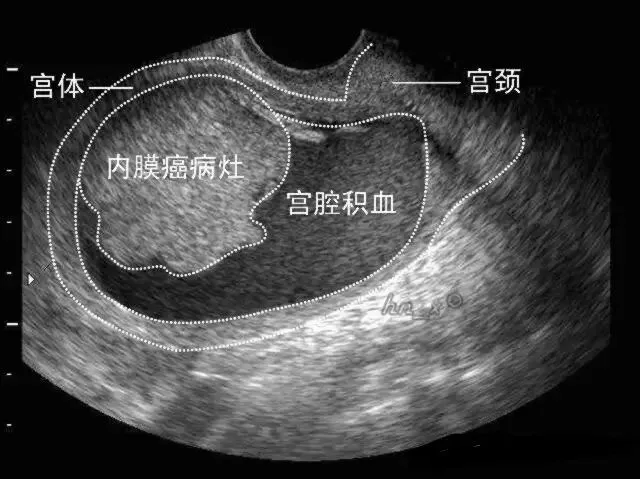

子宫内膜癌

●是指发生于子宫内膜的癌,又称宫体癌。

●二维超声表现:子宫内膜增厚、当病变累及肌层时局部内膜与肌层界限不清、早期子宫外形轮廓多无明显改变。

局灶性子宫内膜癌宫腔积血声像